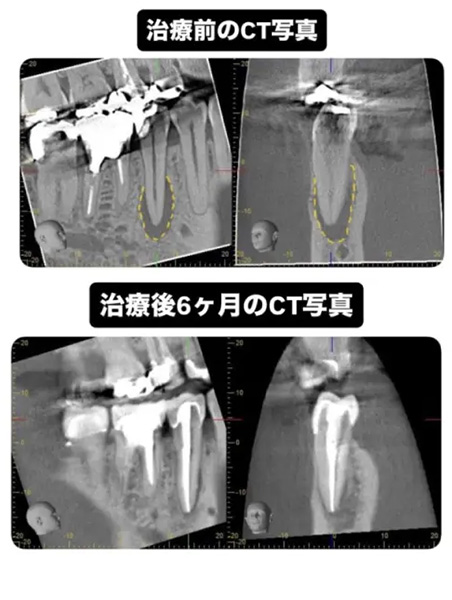

CASE1:【難症例】パーフォレーション(穿孔)をMTAセメントで修復した根管治療

主訴:他院でジルコニア治療後に再発した根尖病変

レントゲン画像にあるように、根管治療を行った後、右上の歯のパーフォレーションにはMTAセメントを使用してリペアしました。

(初診時の影がない部分が骨が溶けている様子です)

内側は骨の壁がなくなるほどごそっと溶けていましたが、一目瞭然でバッチリ回復しています!

処置内容:マイクロスコープによる精密リペアとMTA根管充填

無事、骨も回復し痛みや違和感もなくなったのでオールセラミックスをいれました。当院では、他の歯科医院で抜歯と診断された歯の根管治療を日常的に行っています。高性能な治療器具の導入と、治療時にはアシストする衛生士2人を付けることによって、患者様が安心して治療を受けていただける環境を作っています。